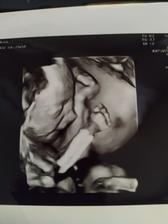

Tehotenstvo #5

Ako rastieme v brušku😘